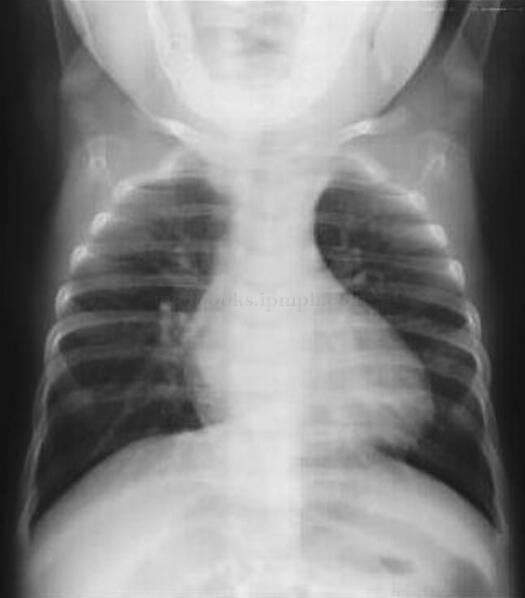

诊断思维提示:胸部X线检查,主要为了评价心脏的形态和肺血的多少。对于区分肺血增多及减少型先天性心脏病有相当大的意义。法洛四联症的患儿特征为肺部血管纹理减少和左心腰凹陷形成“靴形心”。

检查结果:患儿右心房室增大,肺血管纹理明显减少(图73-1)。

图73-1 法洛四联症X线检查